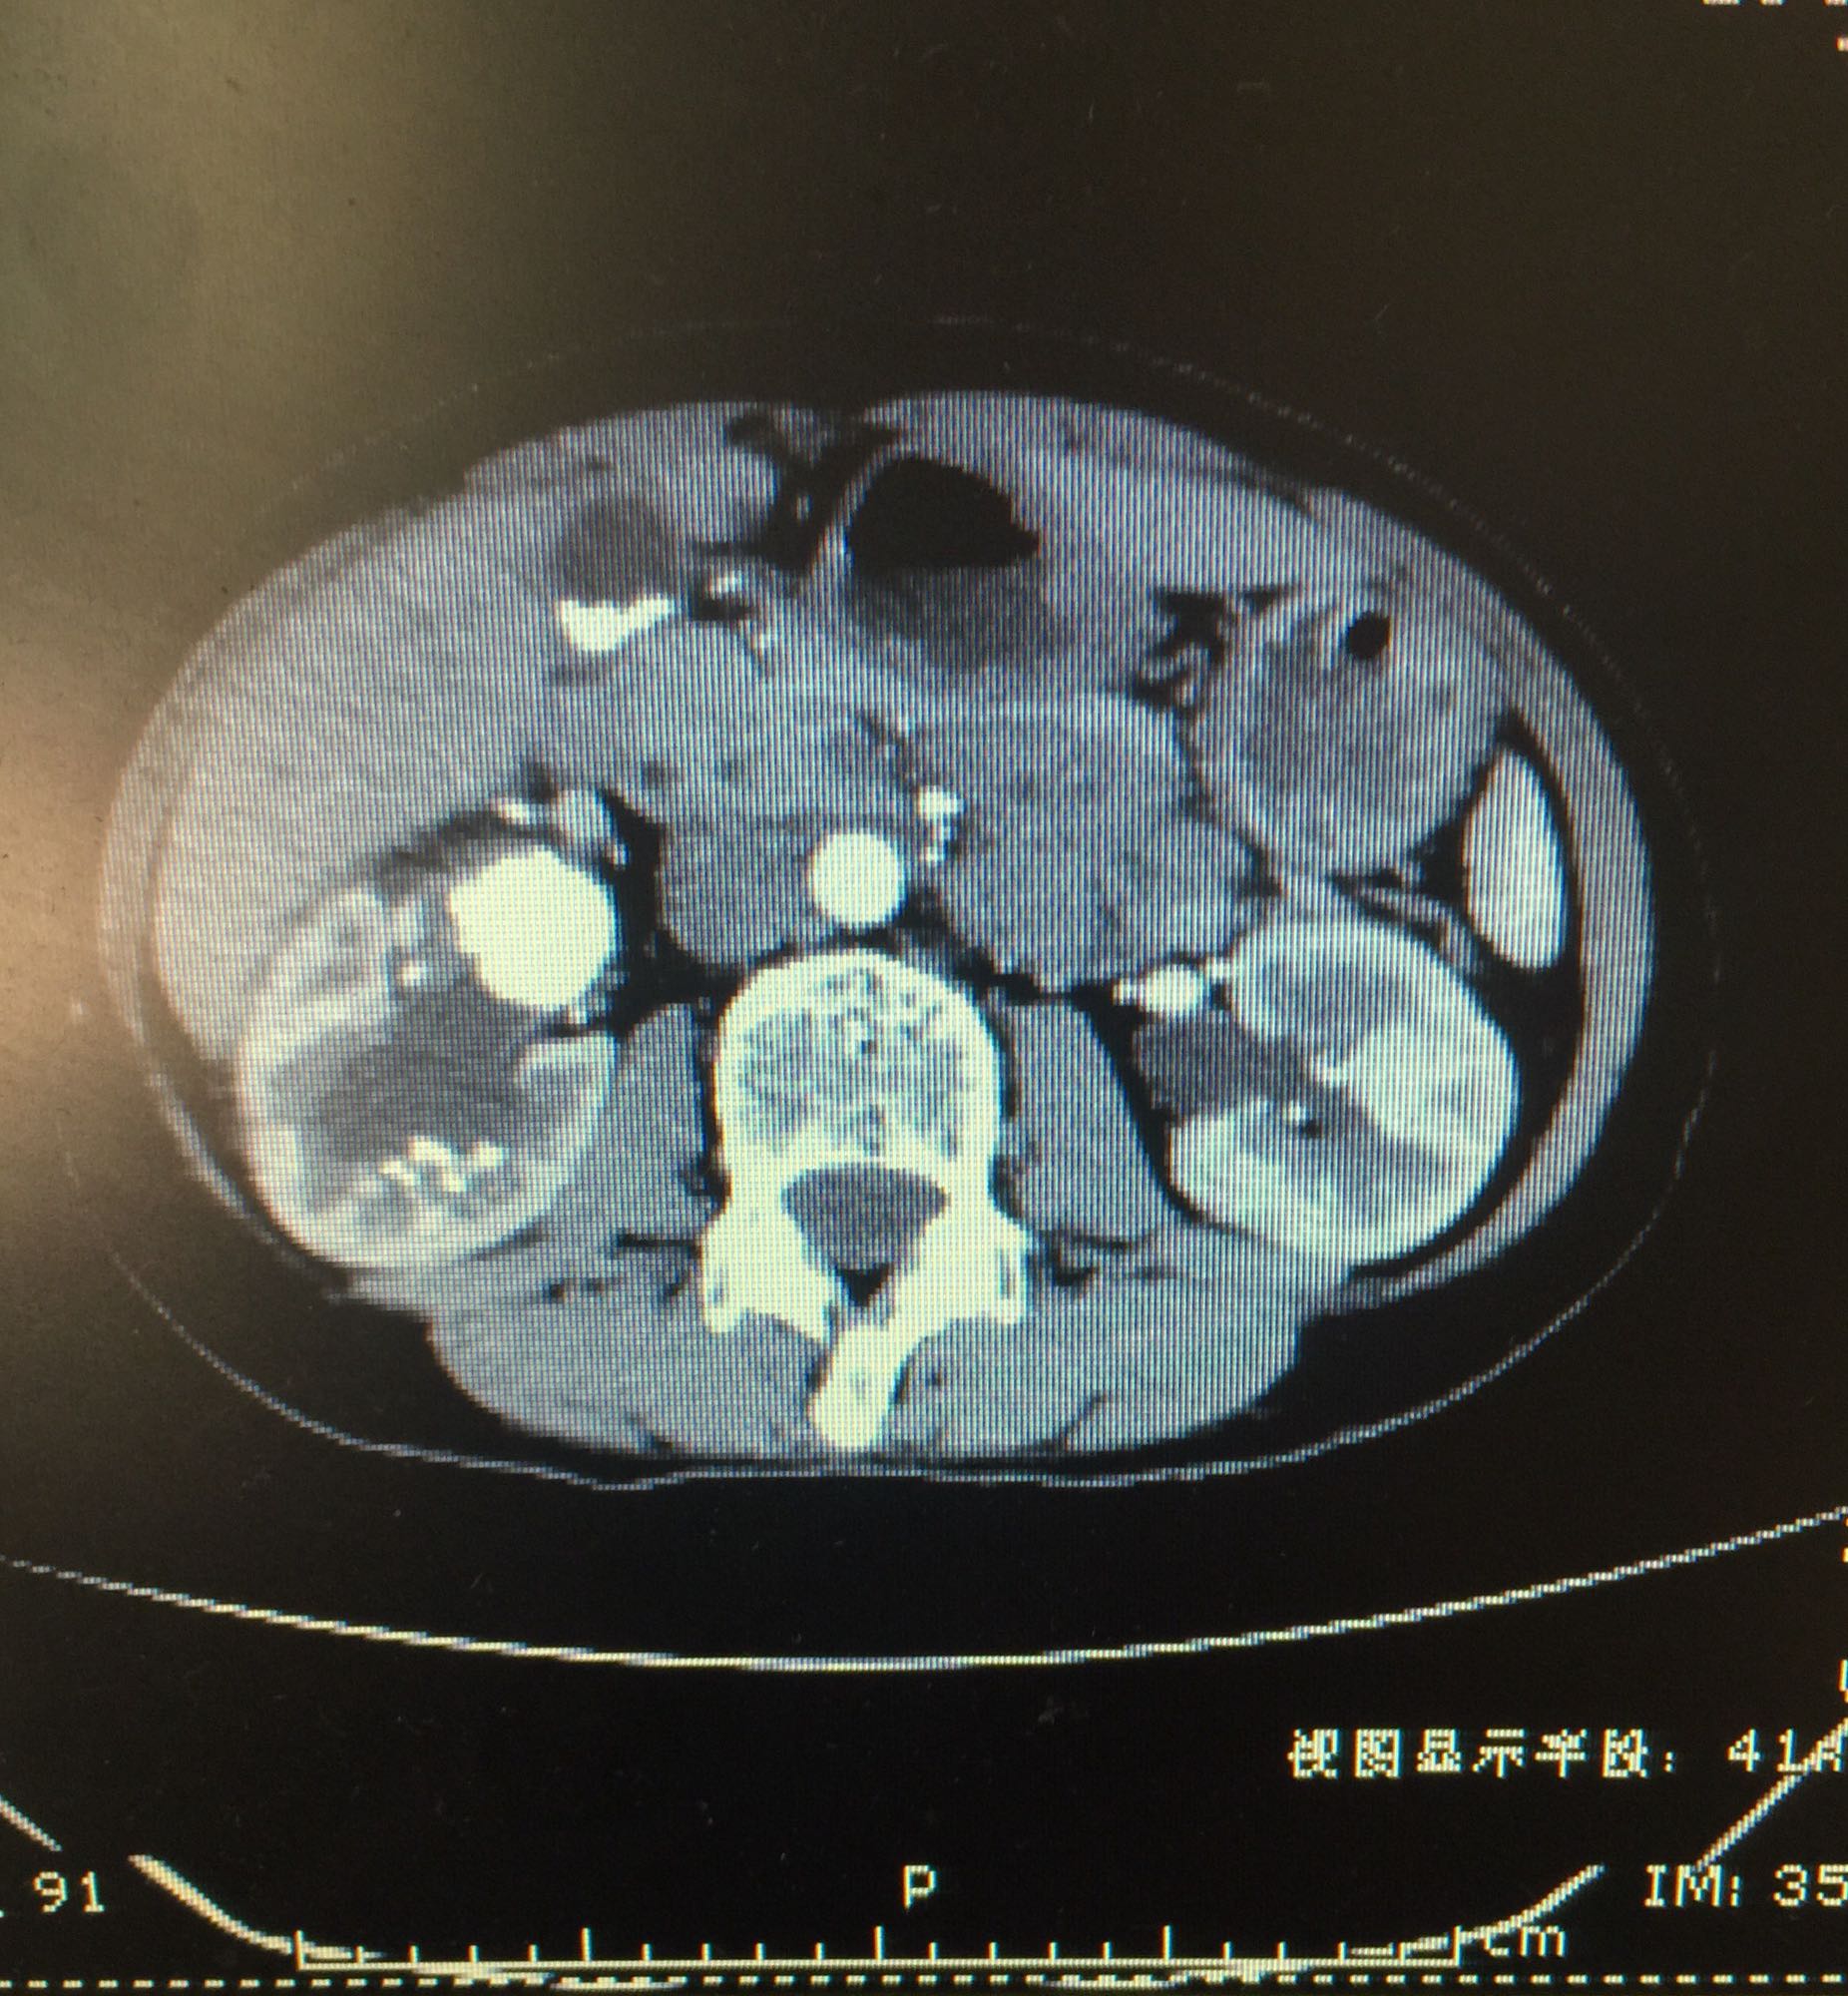

右侧肾脏巨大铸型结石一例

肾盂积水伴输尿管肾盂连接处梗阻 肾结石

60余岁老年男性 因右侧腰痛伴发热1周入院 1周前开始出现右侧腰部胀痛,伴低热,无尿频尿急及肉眼血尿,无其他不适症状 既往高血压,无糖尿病及其他病史

查体右侧肾区轻度叩痛,余症状阴性 辅助检查尿白细胞+++,肾功正常,甲状旁腺激素正常,钙磷比例正常范围

右侧肾脏巨大铸型结石,右肾盂输尿管连接部狭窄? 拟完善GFR测定后决定下一步治疗方案,目前倾向于开放手术。

该患者结石大,且负荷大部分位于肾盂,肾盂几乎被填满,所以考虑是否有右侧输尿管肾盂连接部狭窄可能,结石负荷大,结合上述情况可行开放手术,一期整形 。 但若为UPJO,患者肾脏积水轻,肾脏皮质厚,肾功影响小,可能性相对小。行PCN结合超声吸附,一期清理肾盂内结石应该问题不大。 对于该患者的治疗,不知大家意见如何?